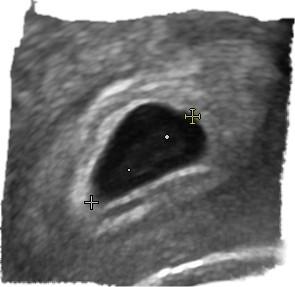

In der 5.ssw sieht man auch noch nicht so viel. Erst in der 7. Oder 8. Woche sieht man mehr plus Herzschlag So sah meins in der 8.ssw aus

Bild zu